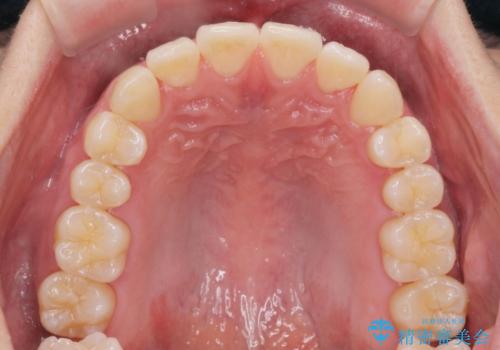

- 20代男性

- ワイヤー

- 10ヶ月

- 取り外しの必要なマウスピース矯正ではなくワイヤー矯正を希望され来院されました。

マウスピース矯正、ワイヤー矯正どちらの方法でも治療は可能ですが、ご要望の通りワイヤー矯正で歯の排列を行っていきます。